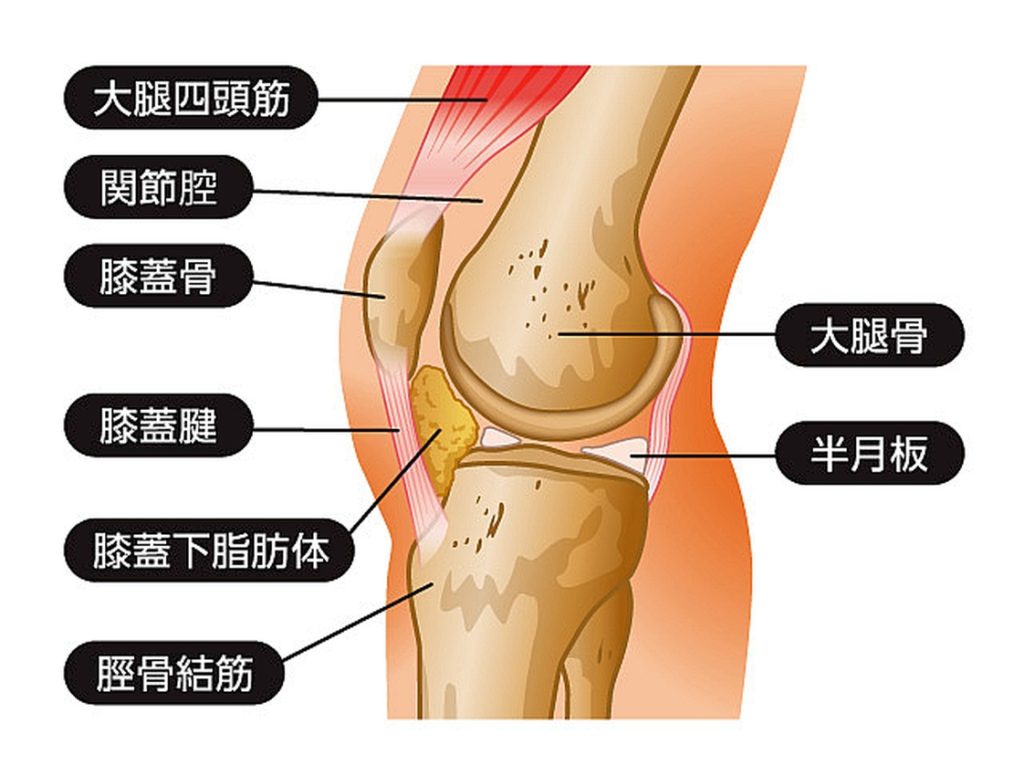

"皿"=膝蓋骨(しつがいこつ)以外の

自分の膝の箇所の骨が何処(半月?)か折れた

とも感じました。以下足の"膝部”の図解となります。

人間の膝というのは極めて複雑な組織で形成されています。

分析出来る事は,相手の肋骨の直下,つまり,みぞおちの上の骨,

"剣状突起部位"と自分の"ひざの皿"が当たったのではと推測しています。

もしくは,

この予想は考えたくないですが,

相手の”浮遊肋骨"部=肋骨の最下部

と自分の膝が当たった可能性も否定は出来ない。

そうなると相手側が"骨折"した可能性が高い。

"浮遊肋骨"という左右2対の肋骨の場所は

胸骨に接しずに浮いているため,

強い外力が及ぶと"折れやすい"のです。